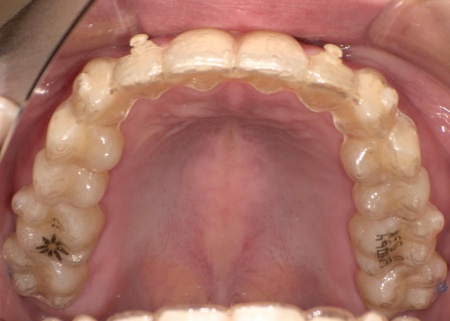

歯並びを改善する方法として、透明なマウスピースを段階的に交換しながら歯を動かしていくインビザラインコンプリヘンシブパッケージによる矯正治療を提案し、同意いただきました。

インビザラインコンプリヘンシブパッケージは装置が透明で目立ちにくく、取り外しができるため食事や歯磨きがしやすい点がメリットです。

一方で、1日あたりの装着時間をしっかり守る必要があり、使用状況によっては計画通りに歯が動かない可能性があります。

まず、患者様専用のマウスピースを作製し、1日一定時間装着していただくようご案内しました。

マウスピースは定期的に新しいものへ交換しながら、少しずつ歯を移動させています。